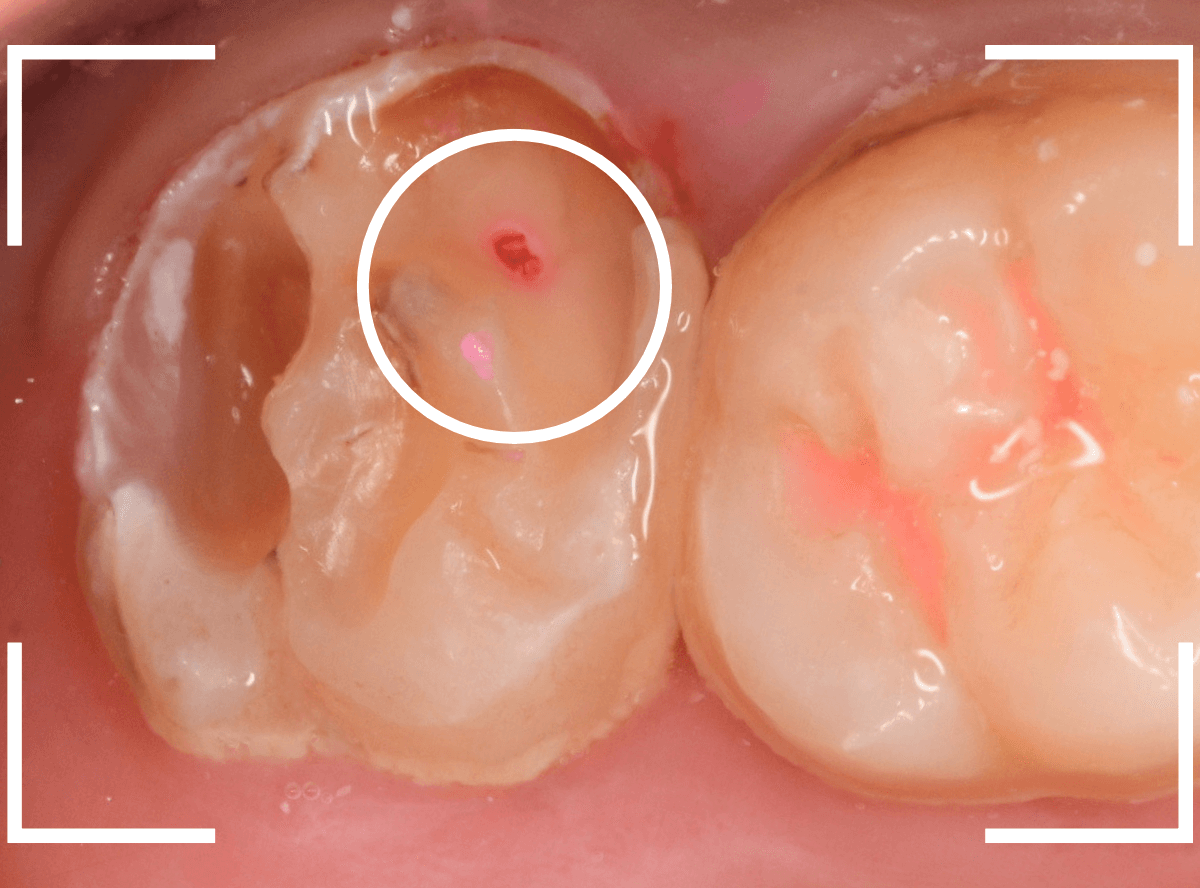

Case.6 上の奥歯の、見えづらいところで虫歯が進行!

こちらも上の一番奥の歯が深い虫歯になってしまった方です。

歯の頬側から奥側にかけて大きな虫歯になっているのがわかります。

カメラではうまく撮れましたが、実際は歯ブラシが届きづらく、虫歯になりやすいところです。

頬側の写真です。

ボコッと虫歯で穴が空いている状況ですが、本人には自覚症状がありません。

自覚症状がないから問題ないわけではない、というのがわかりますね。

治療を開始すると、大きな虫歯が出てきました。

虫歯を全て除去したところです。

赤い小さな点が見えているのは、歯の神経が少し見えてしまっている状態です。

運が悪ければ、神経を取る治療が必要になるかもしれません。

神経を保護するお薬をつめ、セメントで蓋をして、しばらく経過観察をします。

あとは痛みが出ないように祈ります。。。